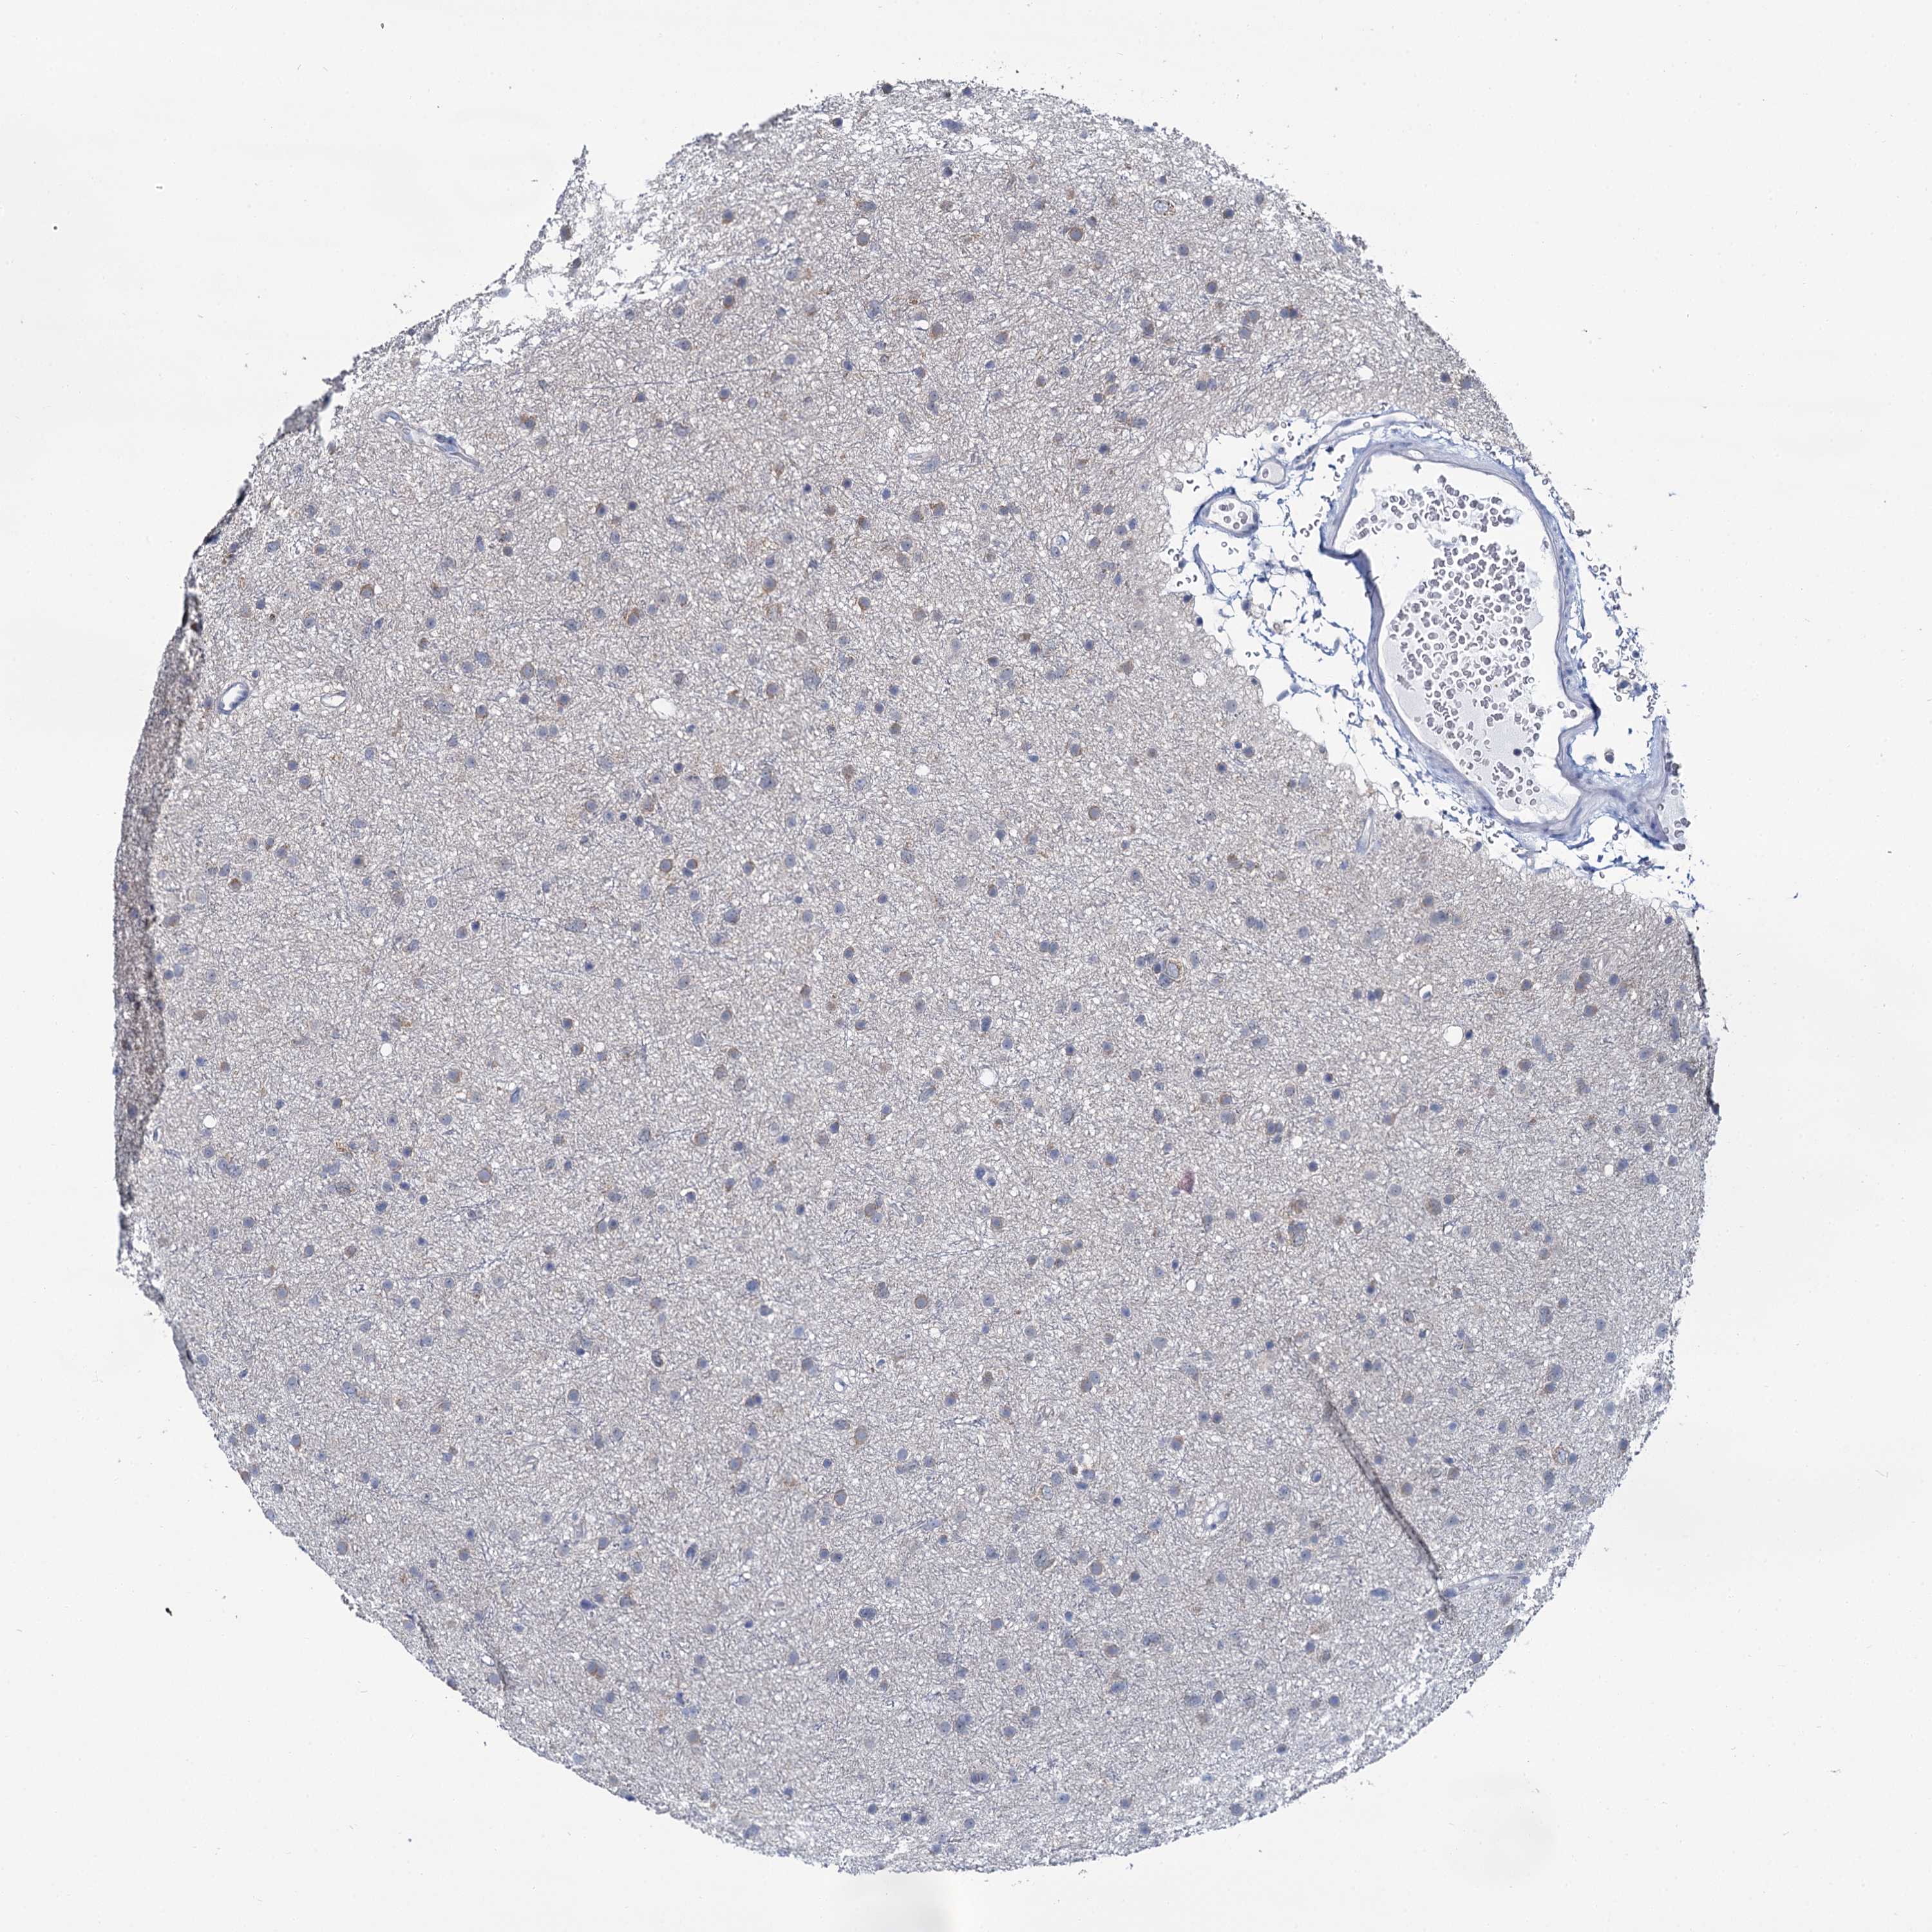

GLIOMA - Protein expressioni

A mouse-over function shows sample information and annotation data. Click on an image to view it in a full screen mode. Samples can be filtered based on level of antibody staining by selecting one or several of the following categories: high, medium, low and not detected. The assay and annotation is described here.

Note that samples used for immunohistochemistry by the Human Protein Atlas do not correspond to samples in the TCGA dataset.

Antibody stainingi

Antibody staining in the annotated cell types in the current human tissue is reported as not detected, low, medium, or high, based on conventional immunohistochemistry profiling in selected tissues. This score is based on the combination of the staining intensity and fraction of stained cells.

Each image is clickable and will lead to virtual microscopy that enables deeper exploration of all samples and also displays staining intensity scores, fraction scores and subcellular localization as well as patient and tissue information for each sample.

Antibody HPA039451

Antibody HPA039562

Staining

High

Medium

Low

Not detected

Intensity

Strong

Moderate

Weak

Negative

Quantity

>75%

75%-25%

<25%

None

Location

Nuclear

Cytoplasmic/membranous

Cytoplasmic/membranous,nuclear

Glioma, malignant, Low grade

Glioma, malignant, High grade

Glioblastoma, NOS